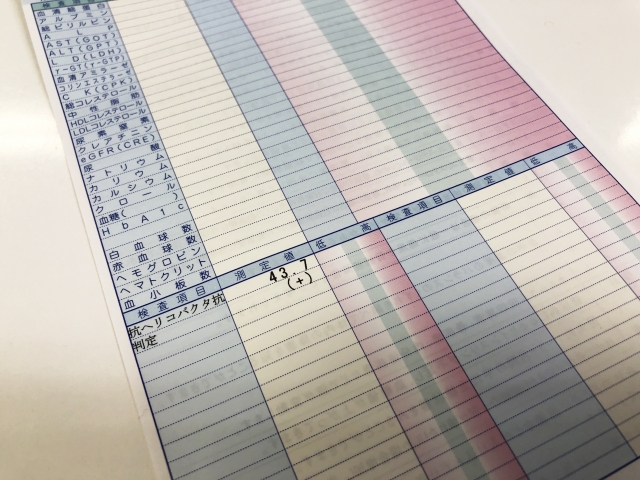

現時点では、SPNの診断に有用な血液検査はありません。